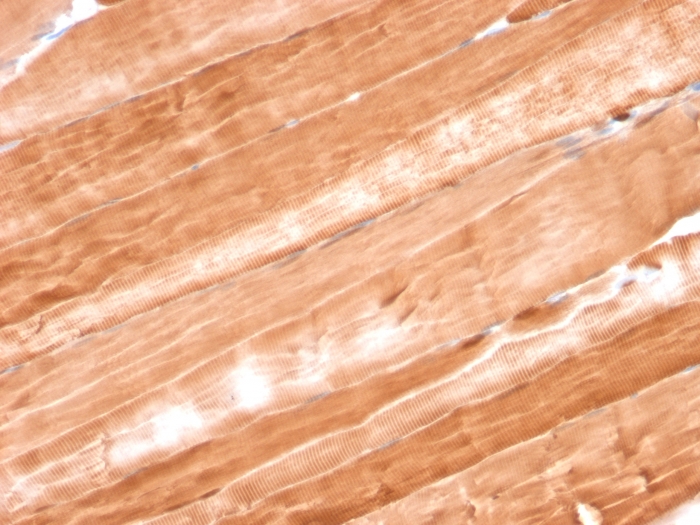

Myoglobin is a cytosolic oxygen-binding protein responsible for the storage and diffusion of oxygen within myocytes. Expression of myoglobin is highest in skeletal and cardiac muscle. Myoglobin is well accepted as an O2-storage protein in muscle, capable of releasing O2 during periods of hypoxia or anoxia.In combination with other striated muscle markers such as vimentin and myogenin, myoglobin is helpful in the identification of rhabdomyosarcoma and tumors with skeletal muscle differentiation. Reportedly, myoglobin is expressed on epithelial cancer cells due to changed metabolic and environmental conditions.

SK-BR3 or T47D cells. Skeletal or Cardiac Muscle.